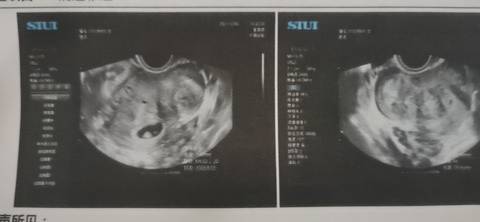

看得懂的帮忙看下,影不影响

你好。我们是判断不了男宝宝跟女宝宝的,孕期定期检查,我觉得宝宝健康就好的。祝心想事成 。

你好,如果有子宫肌瘤的话,你自己也不用担心,后期再看一看,这个会不会慢慢会自行吸收呢?

从结果上面来看目前没有什么影响,不用去管他现在记不记得复查,不要出血就好了